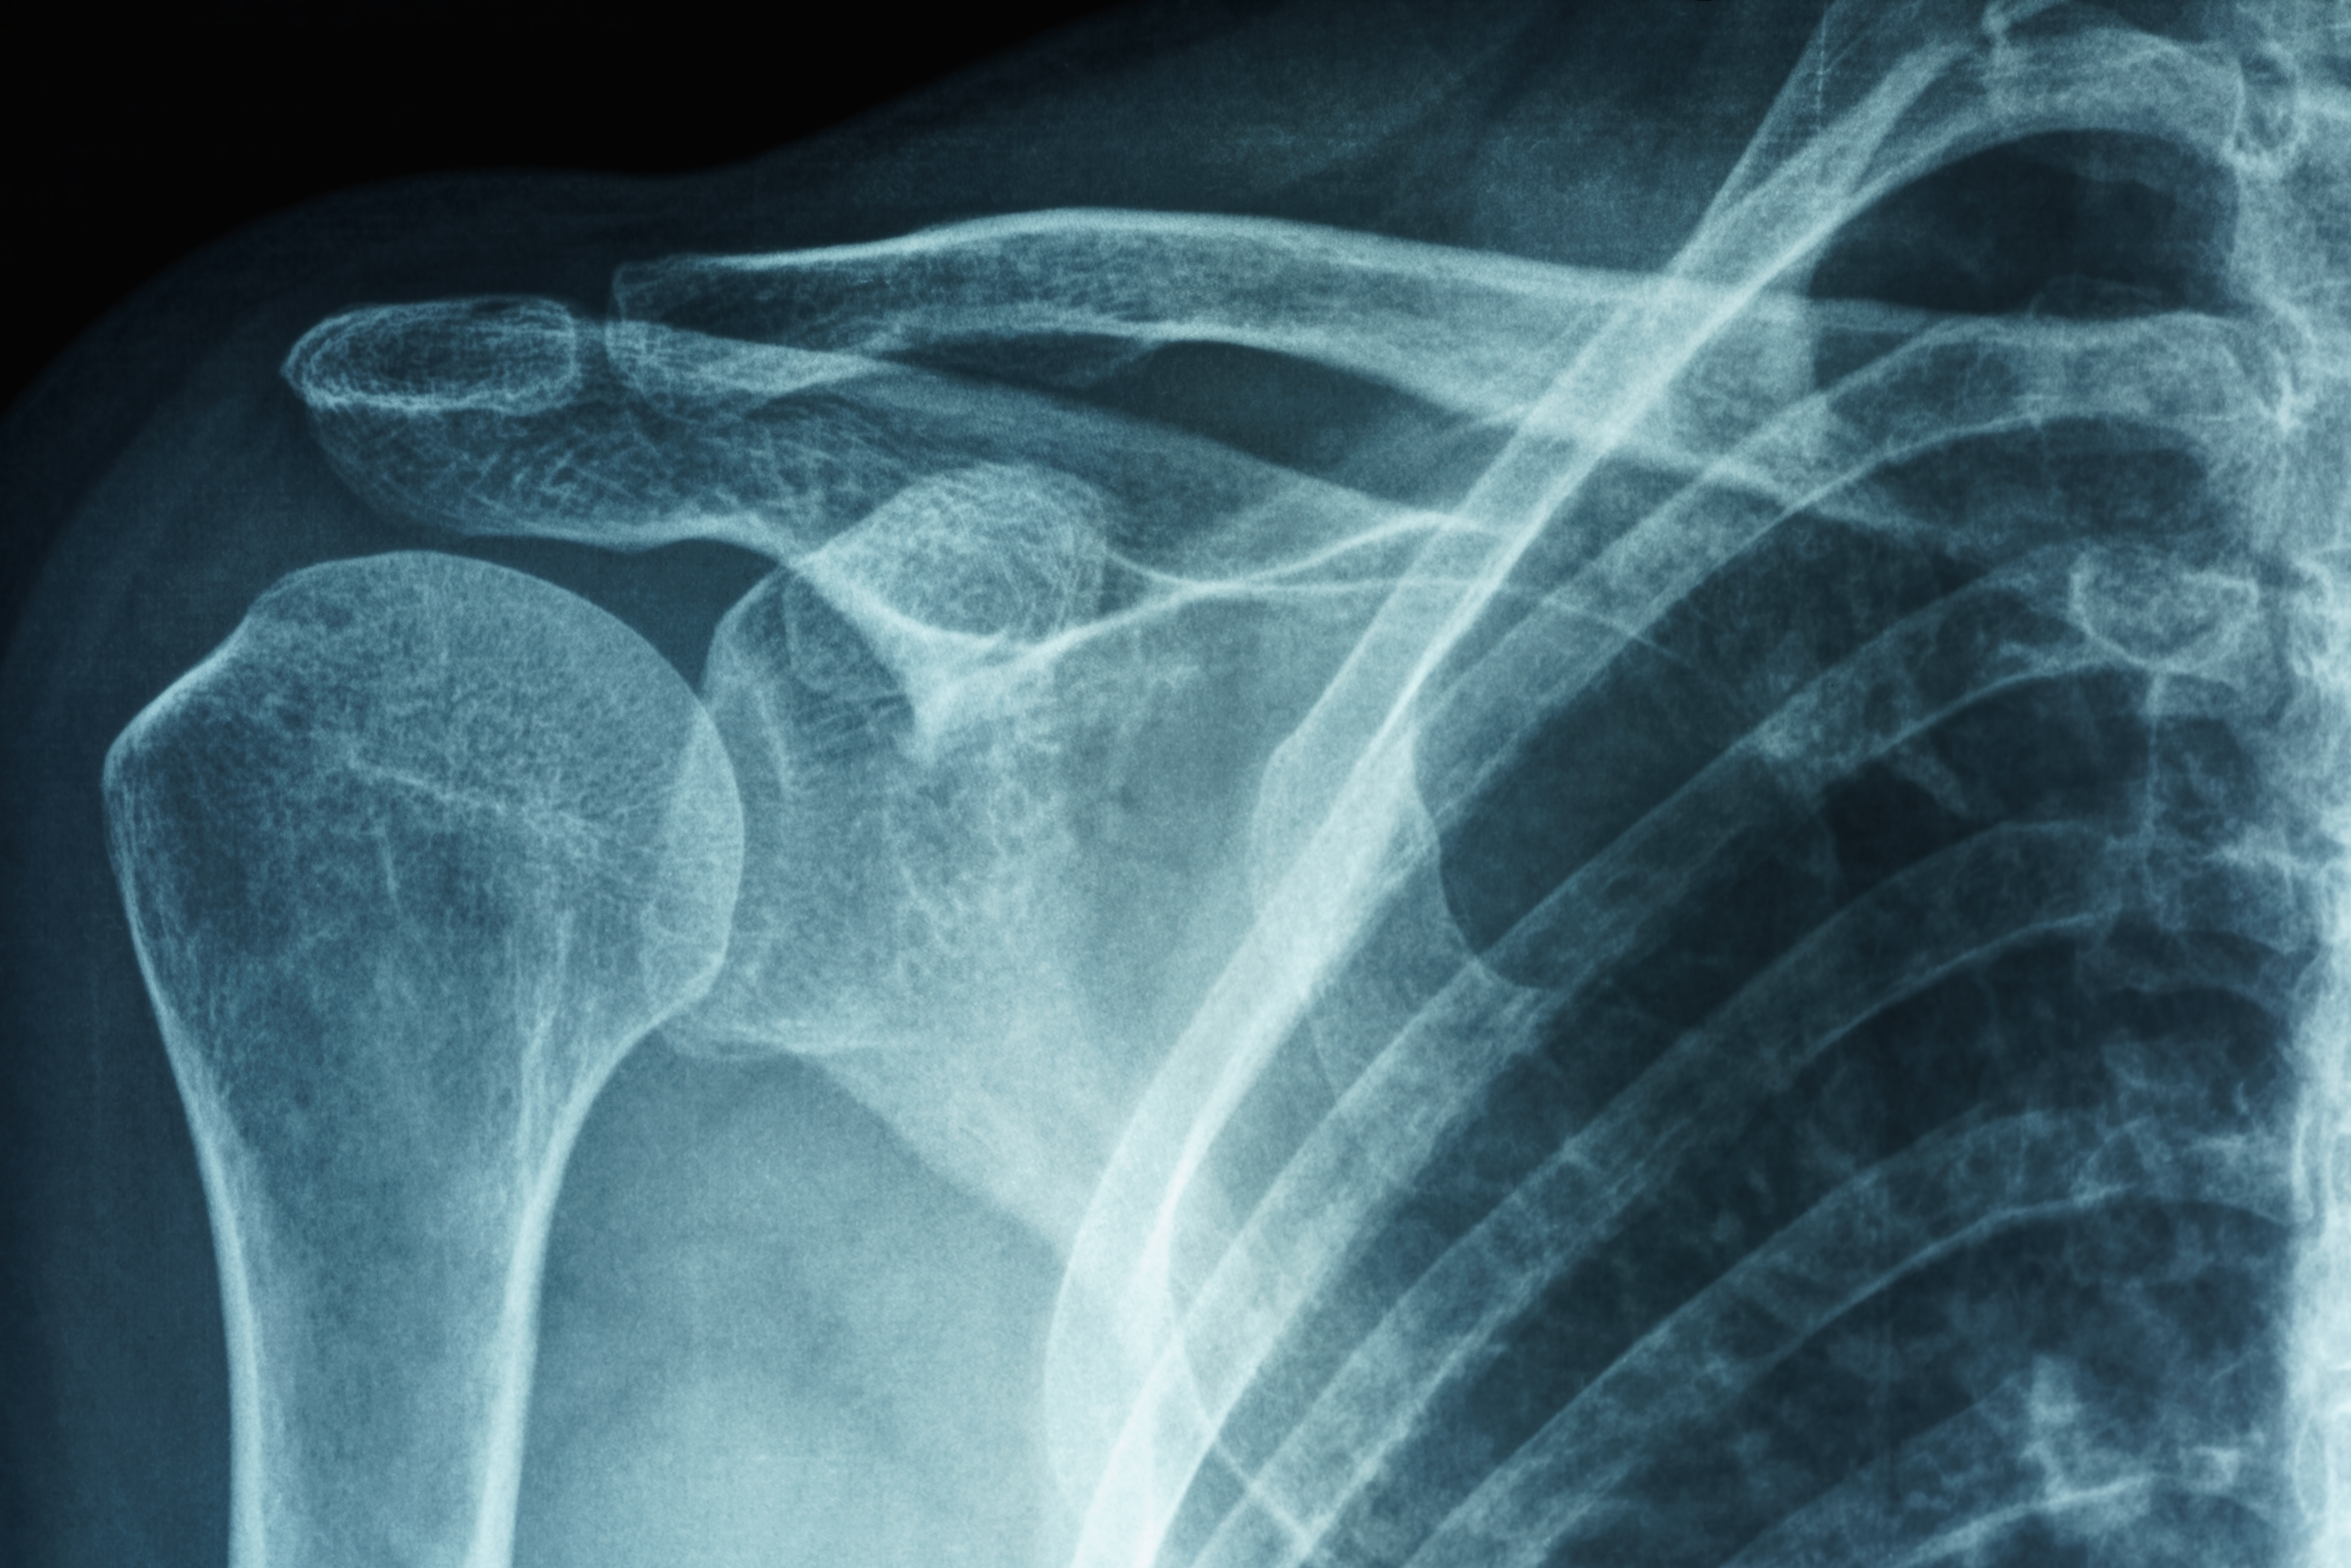

Your shoulder joint is made up of connective tissue, bones, ligaments and tendons. Frozen shoulder (adhesive capsulitis) is a condition in which the capsule of connective tissue in your shoulder joint tightens, causing movements to become painful or difficult.

You will undergo a physical exam. Your OINJ shoulder doctor will test your active and passive range of motion to assess how well you can move your shoulder. Your OINJ shoulder doctor may also have you undergo an X-ray to see if there’s an underlying cause, such as shoulder arthritis or a broken bone.